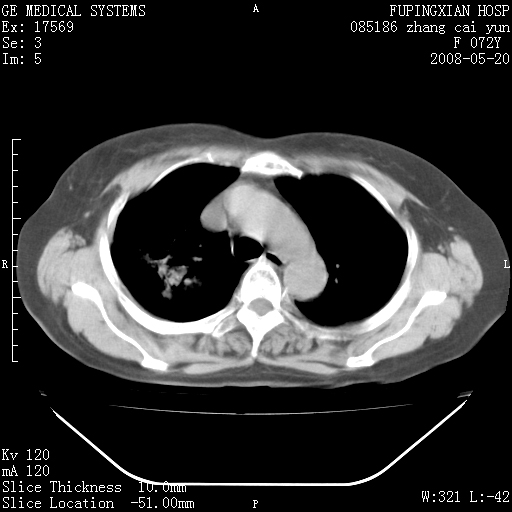

标题: CT13542:发热,咳嗽数日,经抗菌素治疗好转,请大家看排除 [打印本页]

标题: CT13542:发热,咳嗽数日,经抗菌素治疗好转,请大家看排除

有节段性阻塞性肺炎与不张,近段支气管狭窄,周围散在肿大淋巴结影,以周围型肺癌可能性大,建议纤支镜检查。

右肺上叶实变影,内见支气管充气征,右上叶支气管通畅,肺门区未见软组织密度影,抗炎治疗有效,考虑炎症,建议继续抗炎治疗复查。

考虑为:右肺上叶感染性病变。建议:1)继续抗炎治疗后复查。2)必要时行纤支镜检查。

右上肺实变,间内有支气管充气征,考虑炎症,建议抗炎后复查